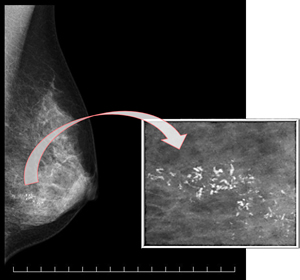

石灰化を明瞭に描写するマンモグラフィ撮影装置

イークでは日本医学放射線学会の定める使用基準を満たしたデジタルマンモグラフィ撮影装置(DR)を設置しています。従来のフィルムとは異なり、デジタルの画素サイズが50~100μmという高精細なシステムFPD(Flat Panel Detector System)を用いて撮影することで、細かい石灰化や腫瘤の形状などを明瞭に描出することができます。